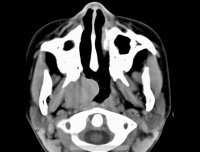

9.腹部B超CT扫描、MRI及胃肠钡餐透视等。